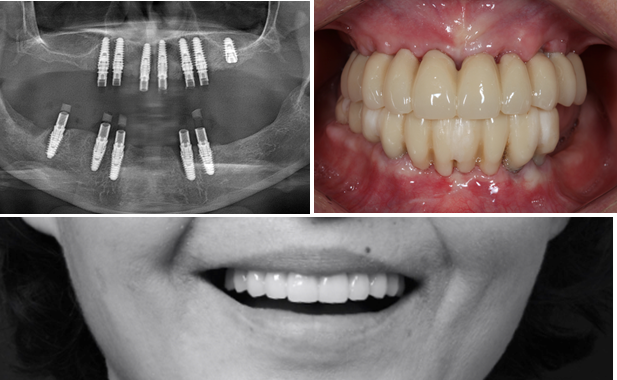

Effective R2STUDIO in complex tooth positioning

- Courtesy of Dr. Jong Cheol Kim, Korea

Dr. Jong Cheol Kim, edentulous, digital full-mouth prosthetics, digital guided surgery, guided surgery,R2 Studio, R2GATE Digital Oral Design, R2GATE DOD,flapless, AnyRidge, R2GATE, R2GATE full surgical Kit

AnyRidge implant system, R2GATE Guide, R2GATE surgical kit, R2GATE DOD, R2 Studio